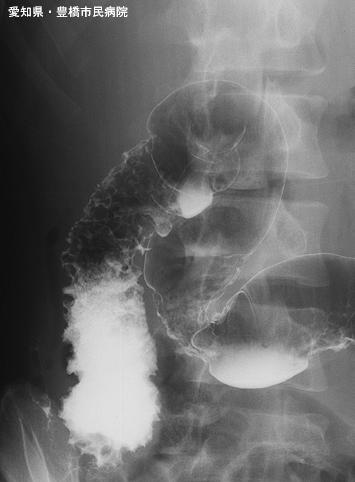

克罗恩(Crohn)病(肠)

伴有食道病变的炎性肠部疾患(疑为节段性肠炎)

Aichi Pref., 丰桥市民病院

男性

15-19

炎症性・溃疡性疾患/克罗恩病

部位(按器官分)

检查方法

40以上